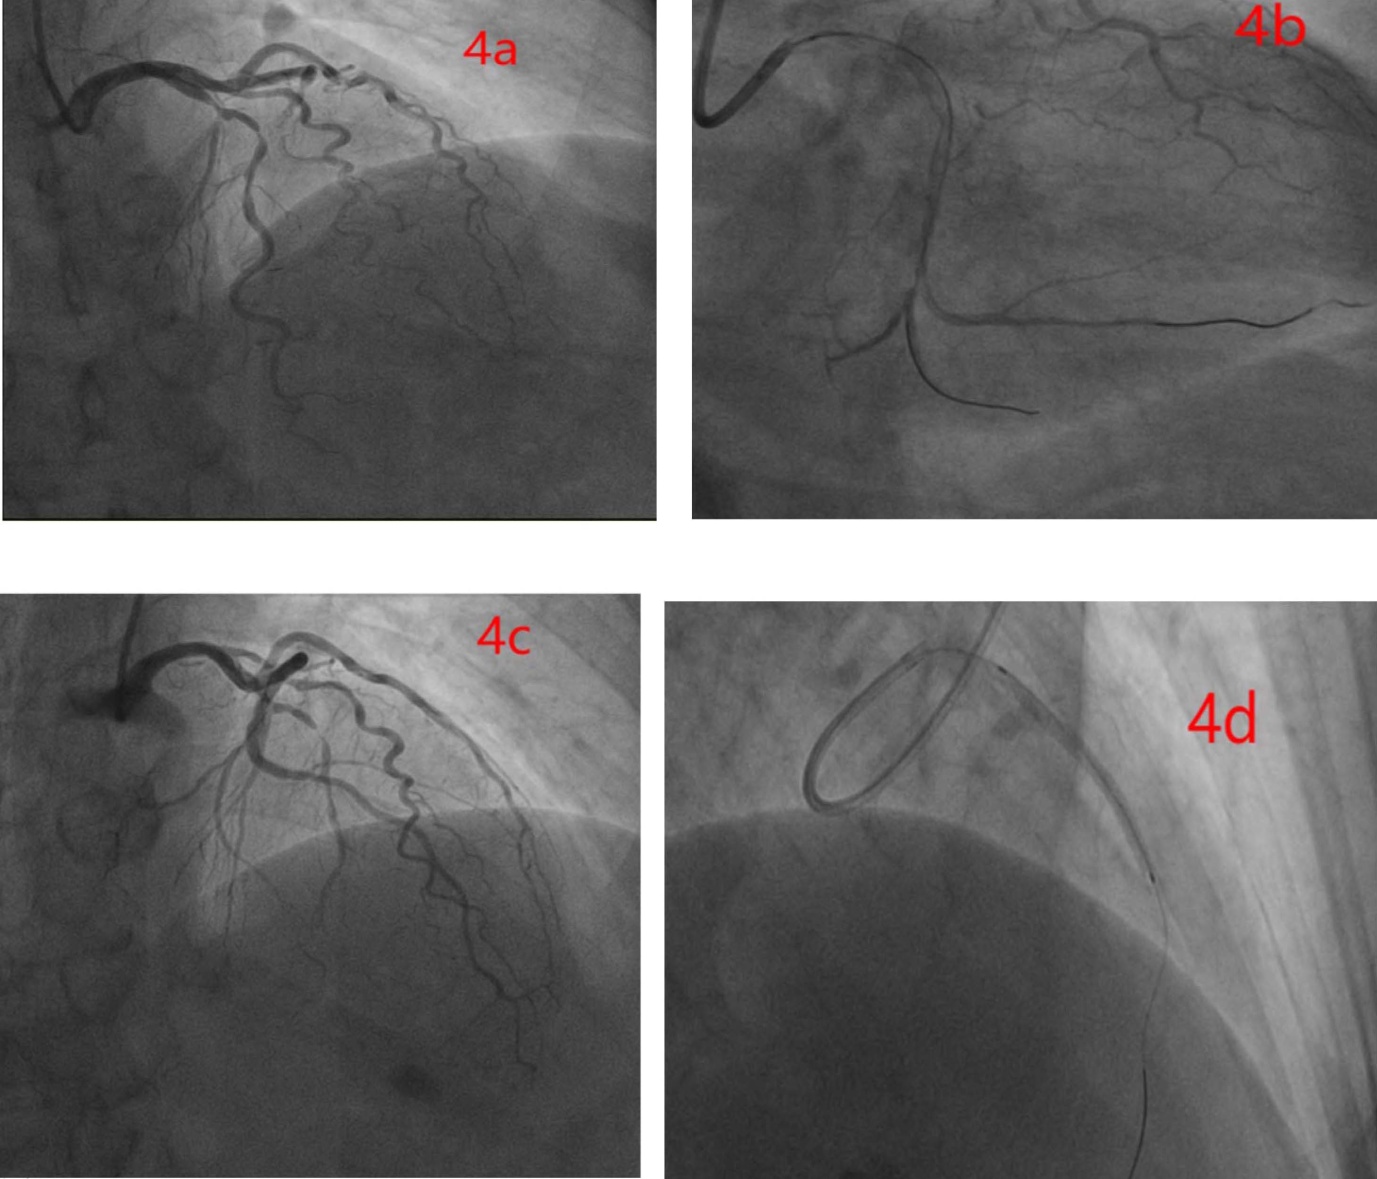

并于出院后2月余再次来我院,复查心脏彩超(见图3),并行冠脉造影(见图4)检查,提示前降支(LAD)近中段弥漫性狭窄约80%~90%,回旋支(LCX)远段弥漫性狭窄约90%~95%,右冠状动脉(RCA)近段狭窄约30%~40%,于回旋支病变处成功行PCI治疗。4月余再次来我院,再次复查心脏彩超(见图3),并行冠脉造影(见图4)检查,LCX支架通畅,于前降支病变处成功行PCI治疗。目前随访,恢复良好。

注:(4a) 为出院后2个月行冠脉造影治疗,(4b) 为放置支架术后。(4c) 为出院后4个月行冠脉造影治疗,(4d) 为放置支架术后。

Figure 4. Coronary angiography and stent implantation imaging

4. 冠脉造影及支架植入影像